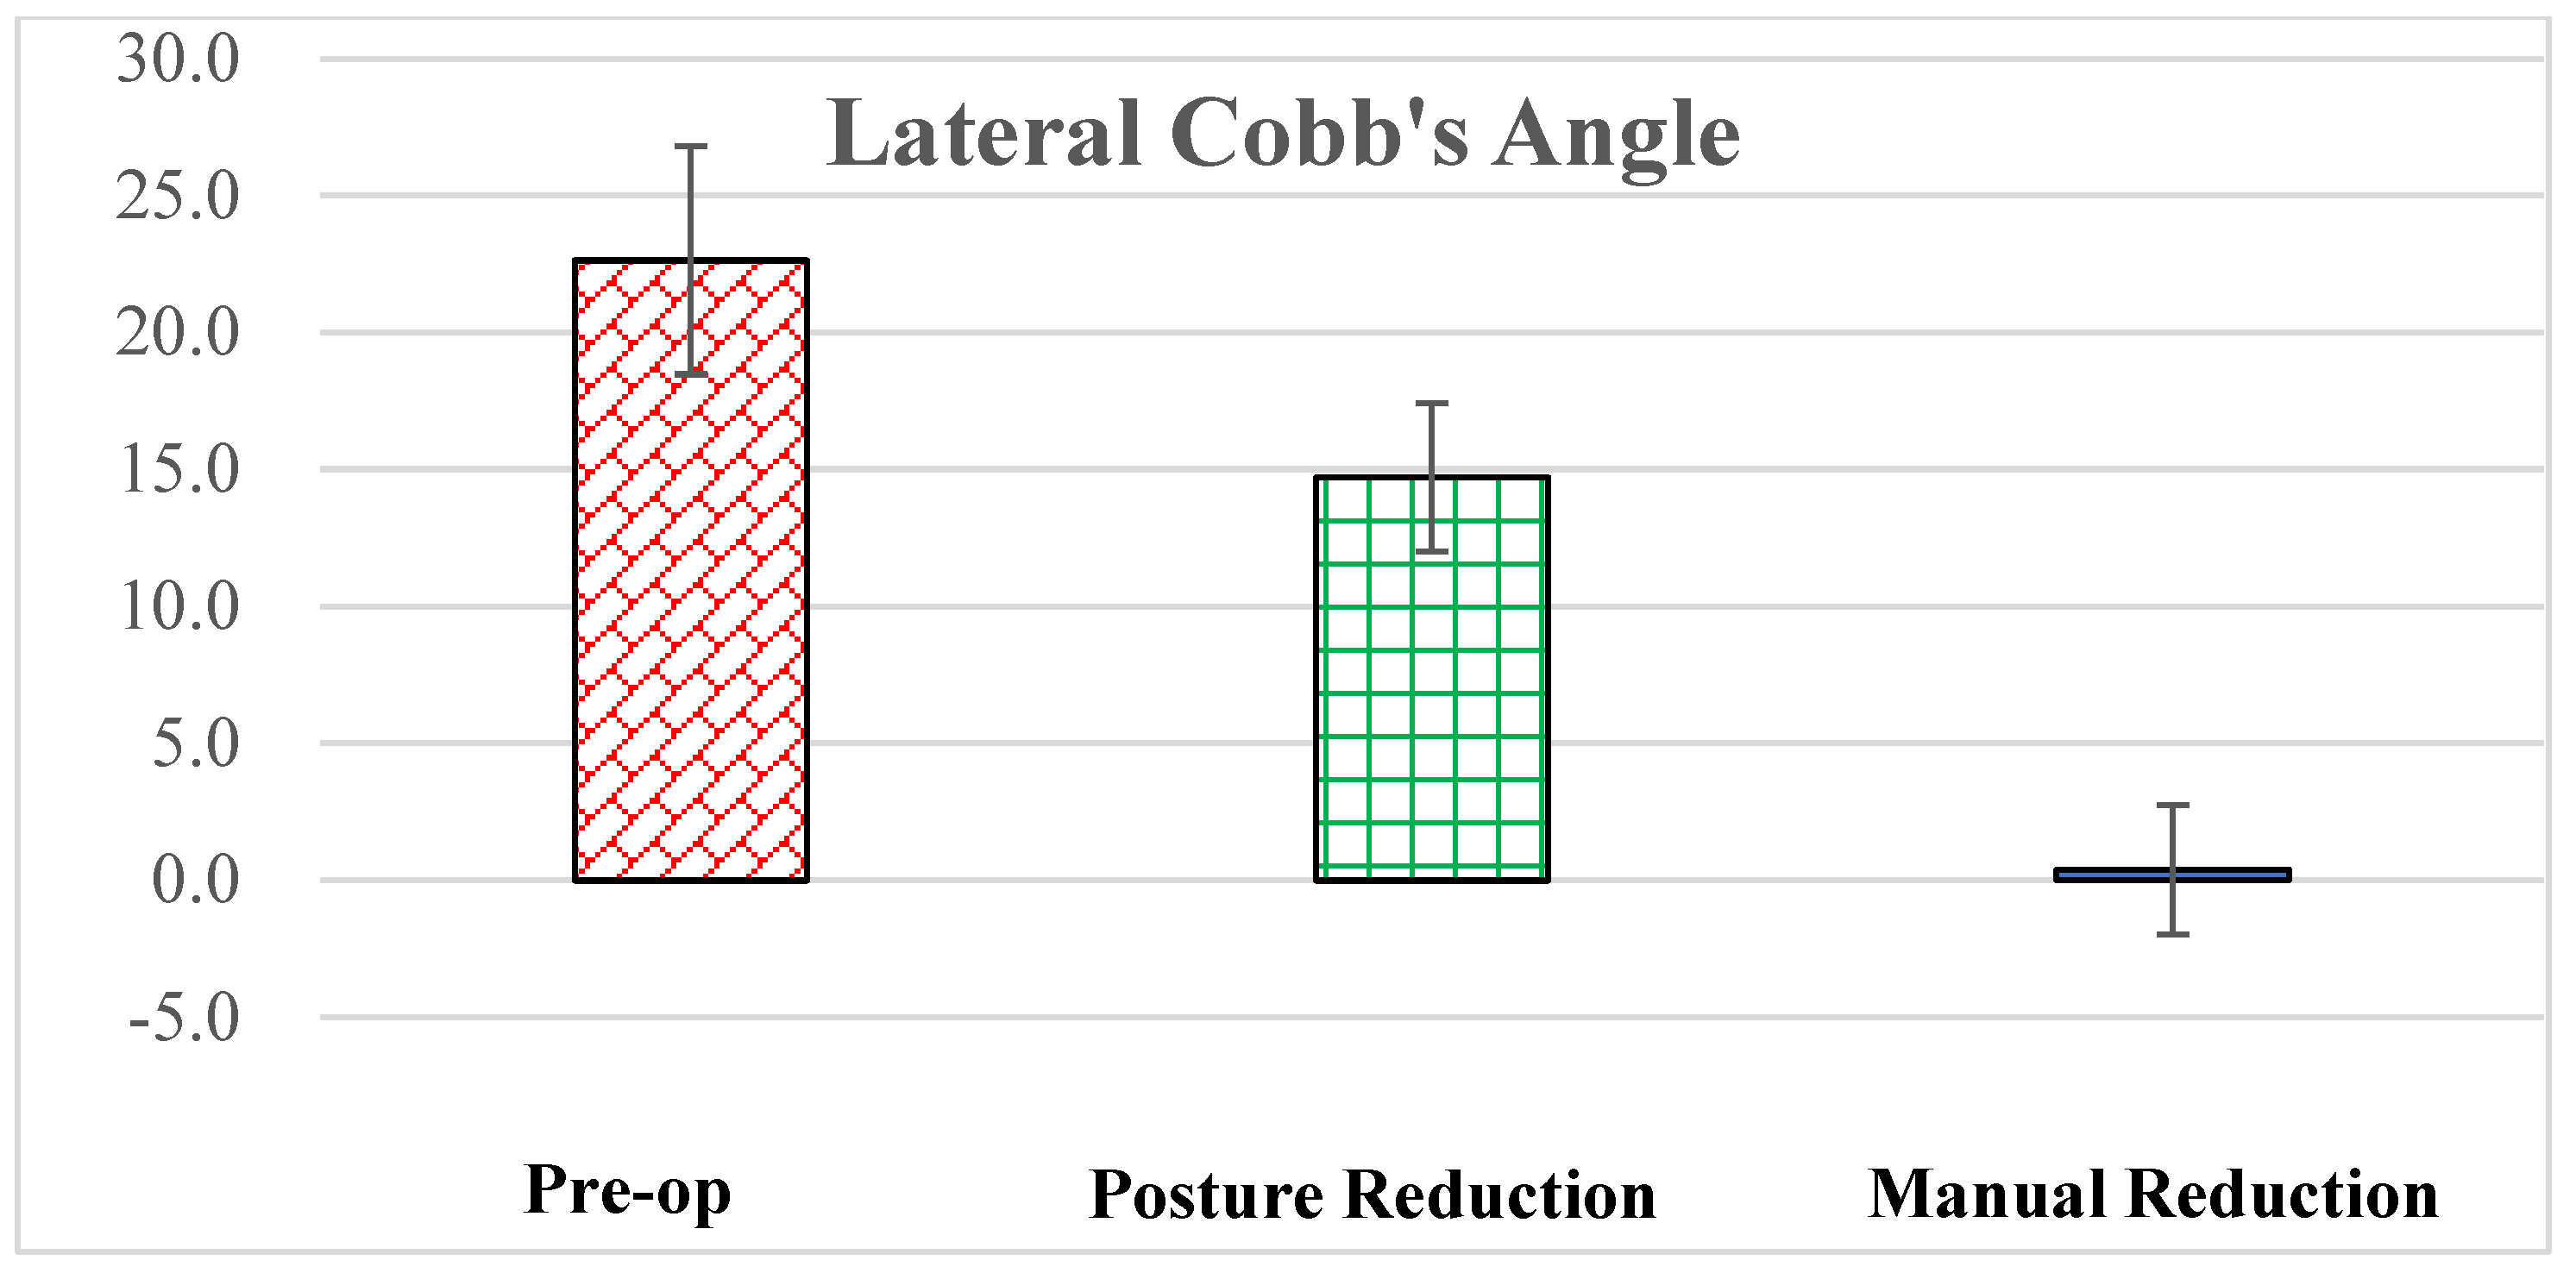

3. Results